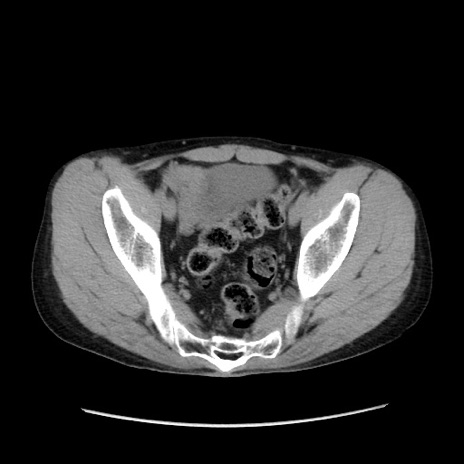

症例37(横断像)

【症例】40歳代 男性

【主訴】腹痛

【現病歴】4時間ほど前に電車に乗車中に臍部上より腹痛出現。徐々に増悪し起立困難となり、救急外来受診。生ものは数日食べていない。今朝お雑煮を食べた。

【身体所見】BT 36.8℃、BP 117/84mmHg、HR 91/min、SpO2 97%、苦悶様、腹部:臍上部広範囲圧痛あり、反跳痛±

【データ】WBC 8100、CRP 0.03